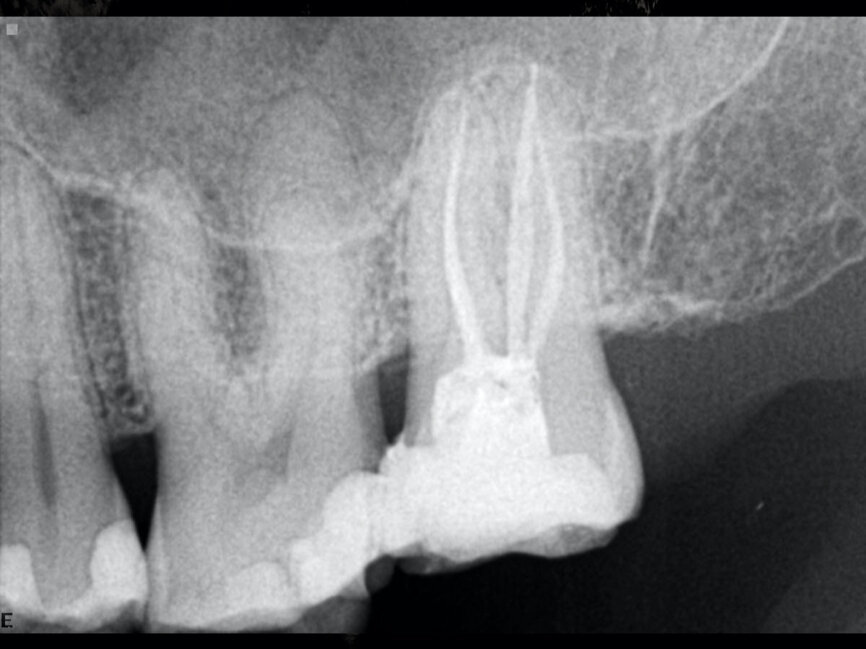

The preoperative radiograph and access cavity under the operating microscope (Images: Philippe Sleiman)

The preoperative radiograph (Fig. 1) revealed that the roots had an uncommon shape, particularly regarding the palatal root, the periodontal ligament and the apex of the mesial root. Upon creating the access cavity (Fig. 2), under the operating microscope, I noticed bleeding from the mesiopalatal angle. Extending the access cavity to that side led to the discovery of a separate canal, which may have been a second palatal or an independent mesial canal.